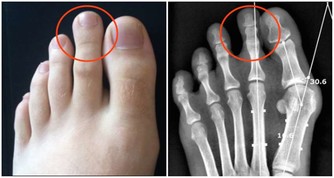

麻疹可能引發嚴重的併發症,如肺炎、腦炎,甚至死亡。未接種疫苗者在接觸麻疹患者後,約90%會感染,顯示出病毒的高傳染性。

接種麻疹疫苗能有效避免因感染麻疹而產生的健康風險,特別是併發症如肺炎和腦炎,這些可能導致長期健康問題甚至死亡。